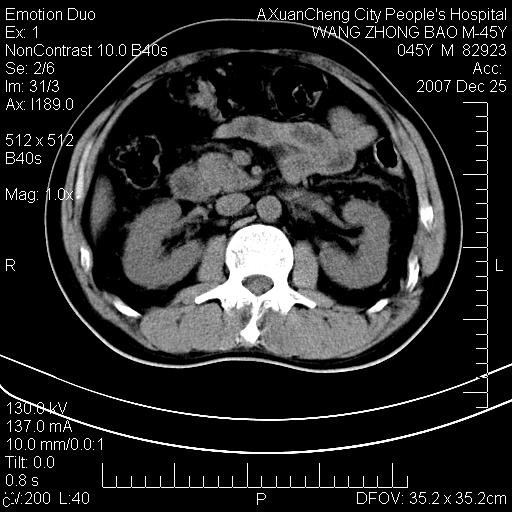

以下是引用qiuleiyu在2007-12-25 18:14:00的发言:[br]胰腺增大,周边渗出改变,肾前筋膜明显增厚,示少量积液.胆囊壁毛糙,周边少许渗出,胆总管壁厚,异常强化,然扩张不明显.结合病程急短;考虑;胆管炎,胆囊炎,胆源性胰腺炎可能大,请结合实验室检查及随访.

以下是引用lisihao在2007-12-25 14:23:00的发言:[br]急性水肿型胰腺炎[br]依据:1、胰腺弥漫性肿大,边缘稍毛糙;[br] 2、双侧肾周筋膜增厚,尤以左侧为甚(重要征象)[br] 3、双侧后胸膜增厚(刺激性炎症);[br] 4、结合病史,查血尿淀粉酶应该可以确诊。